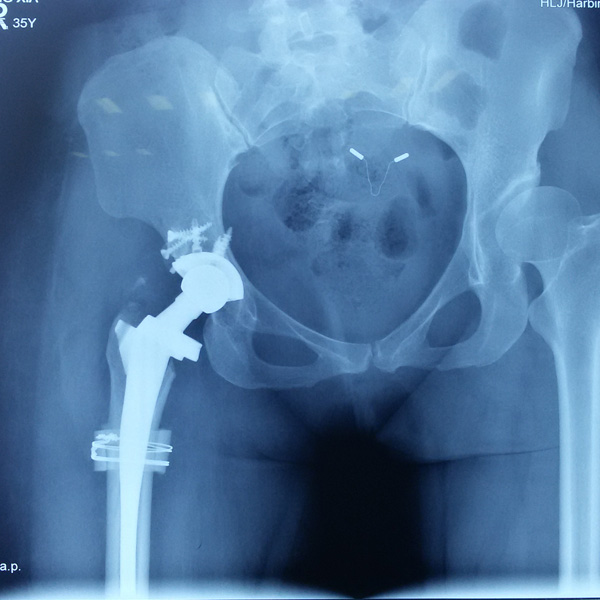

• 髖關節翻修髖關節翻修手術后手術前

髖關節翻修

患者蘇某,女性,11年前因“左髖關節屈曲攣縮畸形”行左側人工全髖關節置換,近來感覺左髖關節疼痛,不敢行走,經“攜生醫療平臺”就診于哈......